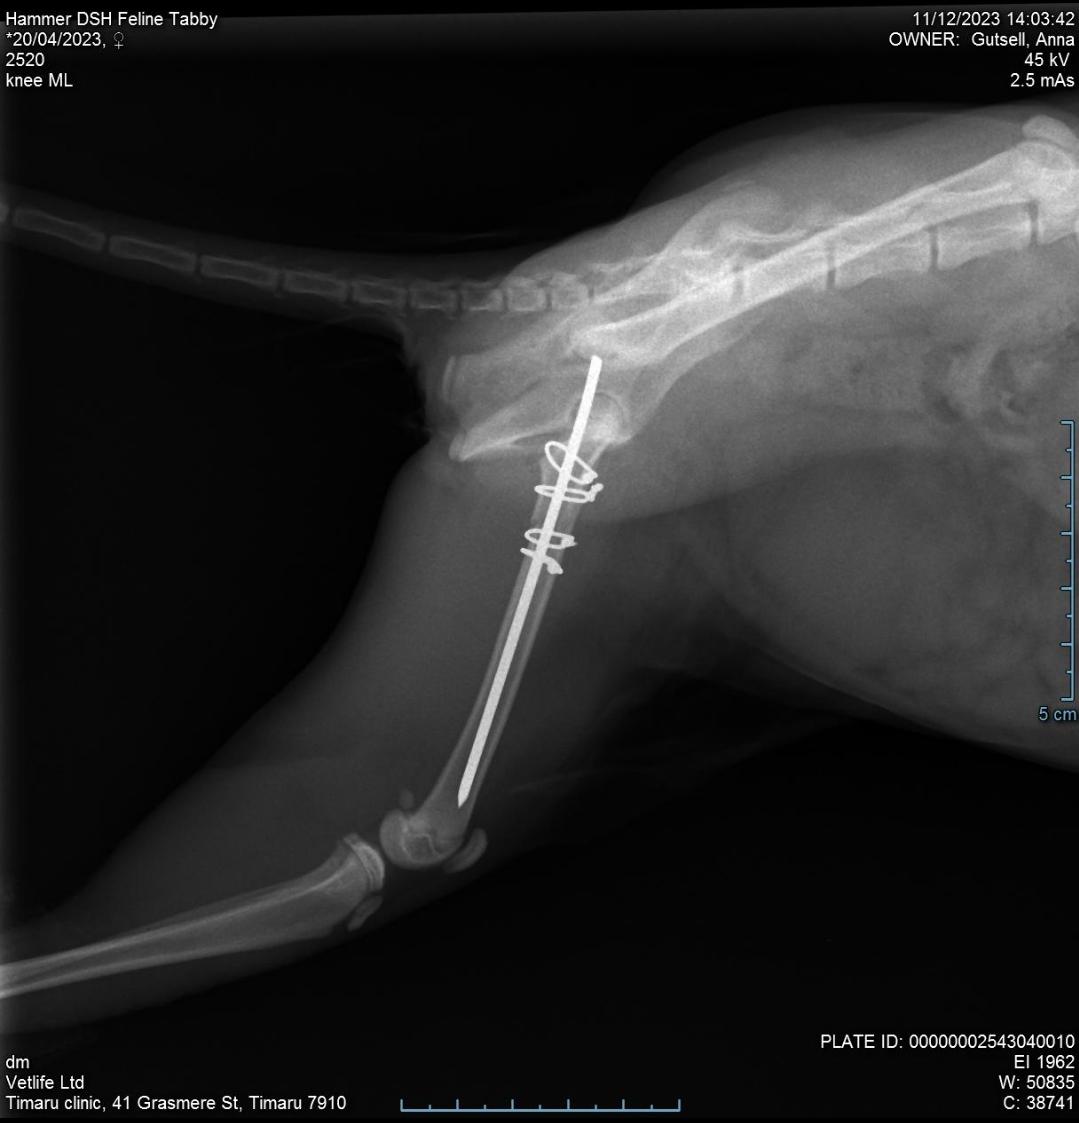

We have the best relationship with our vets not only have other clinics called me to see how Hammer is doing but they have done an amazing job on a very tricky femoral repair on a very small cat. Thank you so much to all that have sent well wishes or donated this is appreciated beyond words her vetbill was slightly higher than estimated but she has an amazing chance to heal now. We will have follow up appointments and more xrays I'm around 6 weeks to check on everything now she has 6 weeks of crate time to heal.